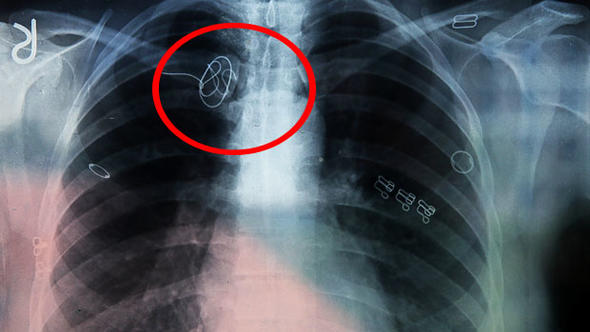

Kütahya’nın Simav ilçesinde yaşayan Hacer Yıldırım’a, 2015 yılında İzmir’de geçirdiği ameliyatın ardından artan ağrıları nedeniyle gittiği hastanede vücudunda kateter teli unutulduğu, telin yeni bir ameliyatla alınamayacağı ve ömür boyu bu şekilde yaşaması gerektiği söylendi.

Adli Tıp Kurumunca hazırlanan raporda, ameliyatın ardından davacının vücudunda kalan “CVP kateter kılavuz teli”nin ömür boyu kullanılacak kan sulandırıcı ilaçlarla hayati tehlike oluşturmayacağı belirtilerek, benzeri cihaz parçalarının yıllarca bu şekilde damarda kaldığı, bu tür durumlarda yeni bir cerrahi müdahalenin hastaya bırakılması gerektiği ifade edildi.